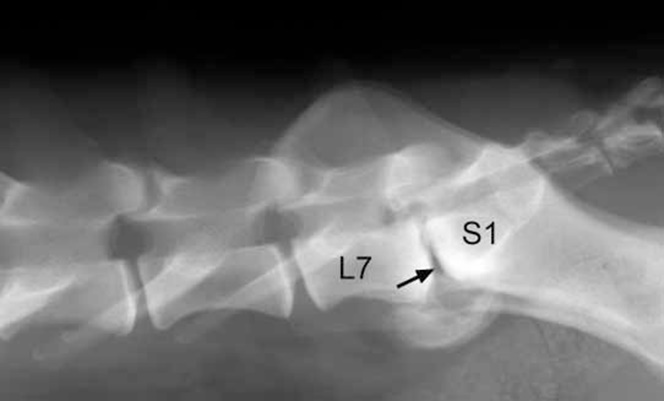

Το βέλος δείχνει την πάχυνση του μεσοτόξιου συνδέσμου που σε συνδυασμό με τη προβολή του μεσοσπονδύλιου δίσκου προκαλούν συμπίεση στην ιππουρίδα.

Ακτινογραφία οσφυοϊερής μοίρας της σπονδυλικής στήλης που απεικονίζεται το φαινόμενο κενού και κοιλιακή παραμορφωτική σπονδύλωση μεταξύ Ο7-Ι1